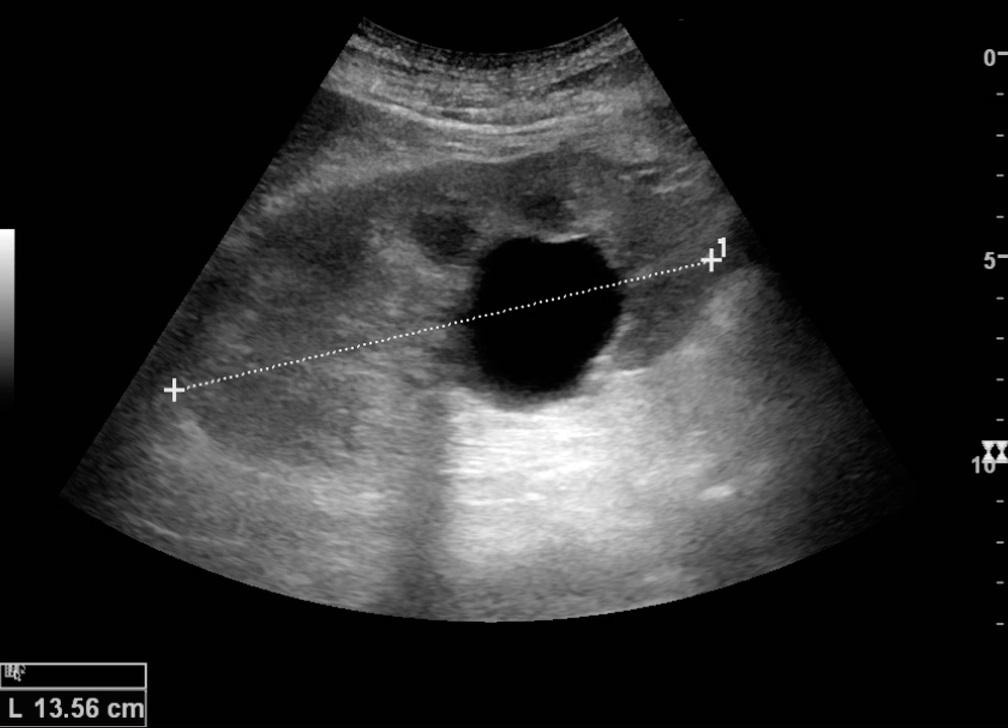

Сценарий довольно частый: на УЗИ «находка» — «киста правой (или левой) почки».

Обычно дальше идут паника — а вдруг это рак и десятки противоречивых советов из интернета. Знакомо? Давайте действовать спокойно. В большинстве случаев киста почки — особенность, с которой можно спокойно жить. Главное — понимать, какая именно это киста и что с ней делать. Разбираем вопрос подробнее с врачами Кутузовского центра Evolutis Clinic. Киста — это замкнутая полость в ткани почки, заполненная жидкостью. По сути, небольшой «пузырек» или «мешочек». Ключевой момент — киста — это доброкачественное образование. Кисты бывают одиночными или множественными, врожденными или приобретенными и, самое главное, простыми или сложными — именно от этого зависит тактика. Простая киста — это самый частый и самый безопасный вариант кисты в почке

Что такое киста почки

Киста — это замкнутая полость в ткани почки, заполненная жидкостью. По сути, небольшой «пузырек» или «мешочек». Ключевой момент — киста — это доброкачественное образование.

Фото Википедия

Простая киста — это самый частый и самый безопасный вариант кисты в почке

Она:

• имеет ровную округлую форму;

• состоит из одной камеры без перегородок;

• с тонкой стенкой и однородным содержимым;

• не накапливает контраст при КТ или МРТ.

Такие кисты встречаются у 20–30% людей, особенно после 50 лет, чаще всего никак себя не проявляют и не влияют на функцию почек.